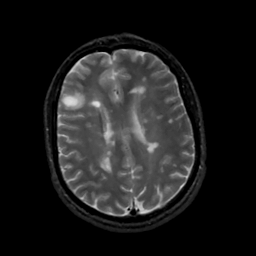

MR Study #5, March 10, 1991 -- Slice #34

[Home][Help][Clinical][Tour 1][Tour 2] Slice 34